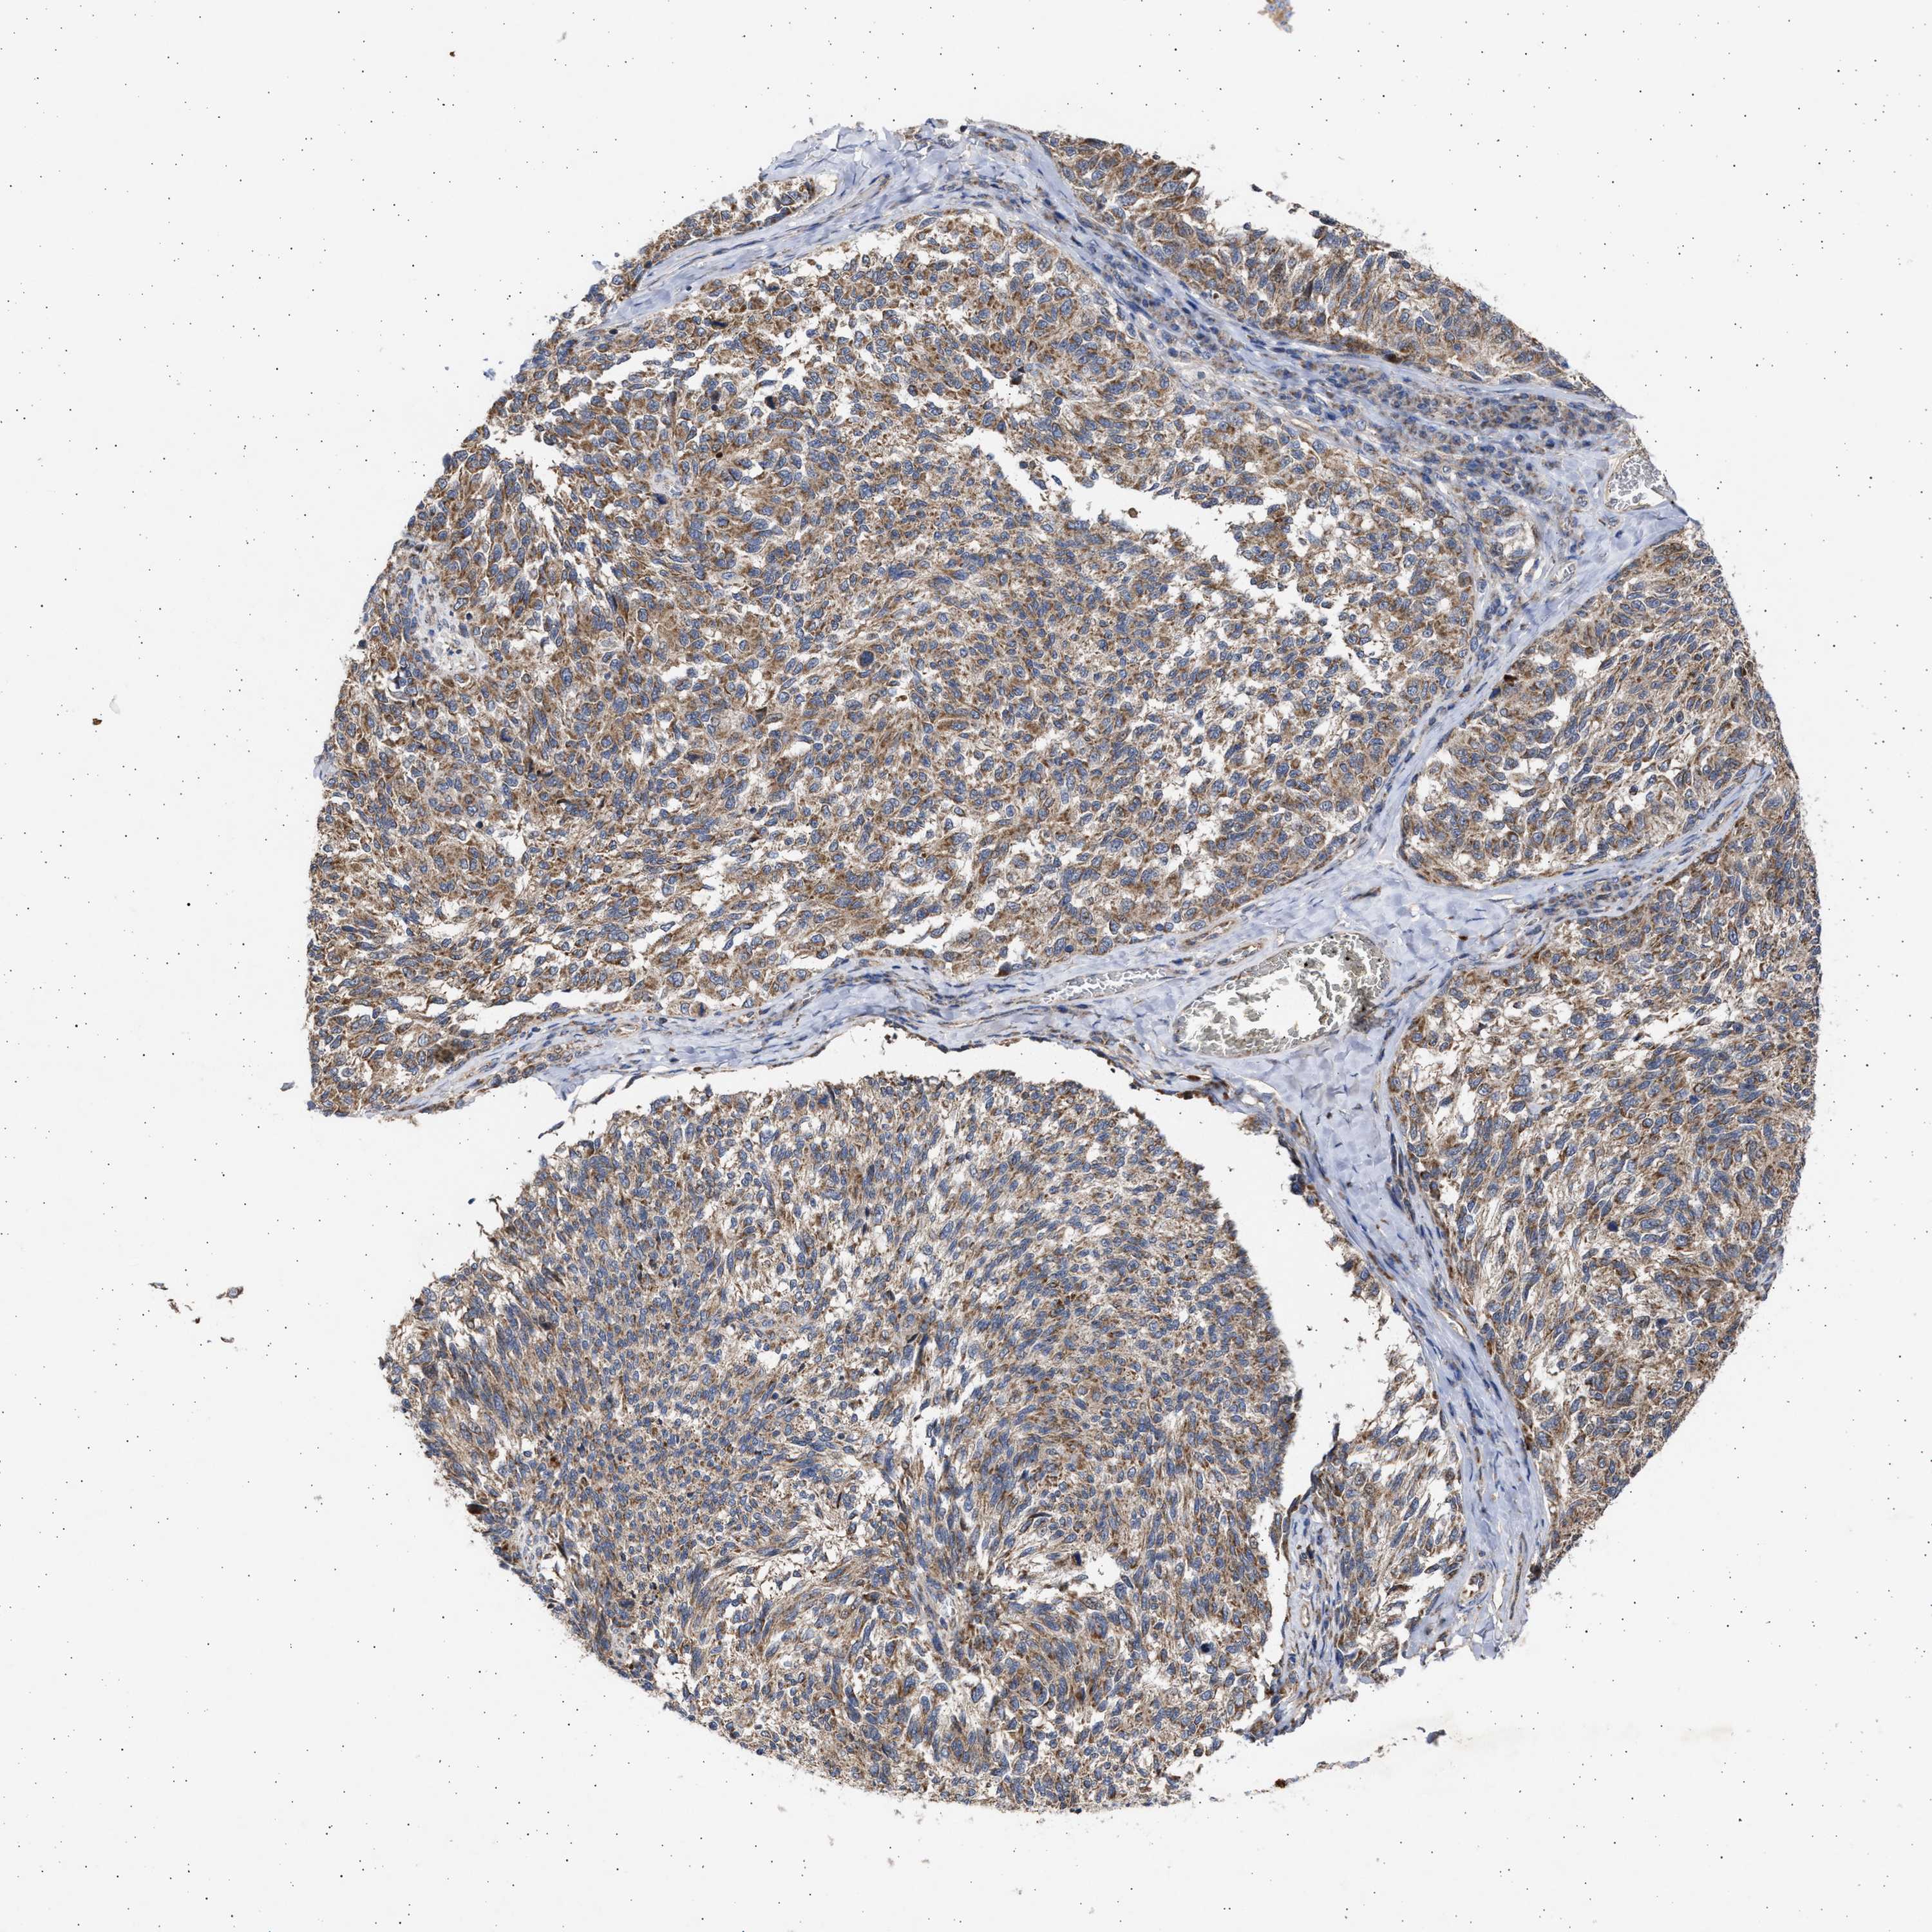

MELANOMA - Protein expressioni

A mouse-over function shows sample information and annotation data. Click on an image to view it in a full screen mode. Samples can be filtered based on level of antibody staining by selecting one or several of the following categories: high, medium, low and not detected. The assay and annotation is described here.

Note that samples used for immunohistochemistry by the Human Protein Atlas do not correspond to samples in the TCGA dataset.

Antibody stainingi

Antibody staining in the annotated cell types in the current human tissue is reported as not detected, low, medium, or high, based on conventional immunohistochemistry profiling in selected tissues. This score is based on the combination of the staining intensity and fraction of stained cells.

Each image is clickable and will lead to virtual microscopy that enables deeper exploration of all samples and also displays staining intensity scores, fraction scores and subcellular localization as well as patient and tissue information for each sample.

Antibody HPA023010

Antibody HPA052380

Staining

High

Medium

Low

Not detected

Intensity

Strong

Moderate

Weak

Negative

Quantity

>75%

75%-25%

<25%

None

Location

Nuclear

Cytoplasmic/membranous

Cytoplasmic/membranous,nuclear

Malignant melanoma, NOS

Malignant melanoma, Metastatic site